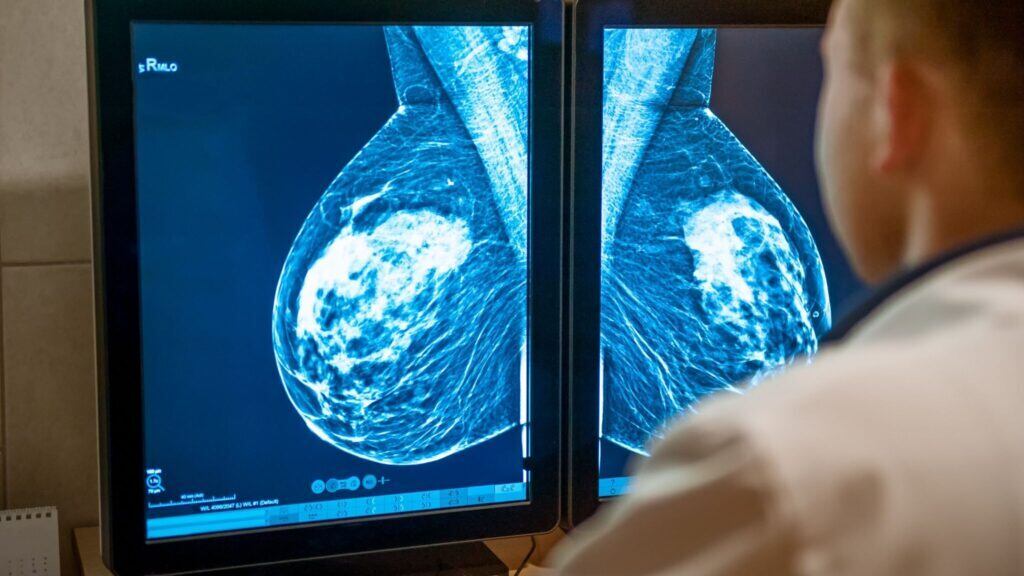

Mamografia em mulheres acima de 80 anos ainda ajuda no diagnóstico precoce

Rastreamento ajuda a detectar câncer cedo e facilitar o tratamento

Tradicionalmente recomendada entre os 50 e 70 anos, uma nova pesquisa indica que mulheres com mais de 80 anos podem se beneficiar significativamente do rastreamento, desde que estejam em bom estado de saúde e tenham expectativa de vida prolongada.

Um estudo recente publicado no Annals of Surgical Oncology analisou 174 mulheres com mais de 80 anos diagnosticadas com câncer de mama entre 2013 e 2020. As mulheres participantes do estudo foram divididas em dois grupos: aquelas que realizaram mamografia nos últimos dois anos e aquelas que não realizaram. Os resultados mostraram:

• Tumores menores e menos agressivos entre as mulheres rastreadas

• Tratamentos menos invasivos, com menor necessidade de quimioterapia, radioterapia ou biópsia de linfonodo

• 55% menos risco de recorrência do câncer

• Redução de 74% no risco de morte

Esses dados reforçam que a detecção precoce tem impacto direto na sobrevida e na qualidade de vida, permitindo intervenções mais seguras e menos traumáticas.